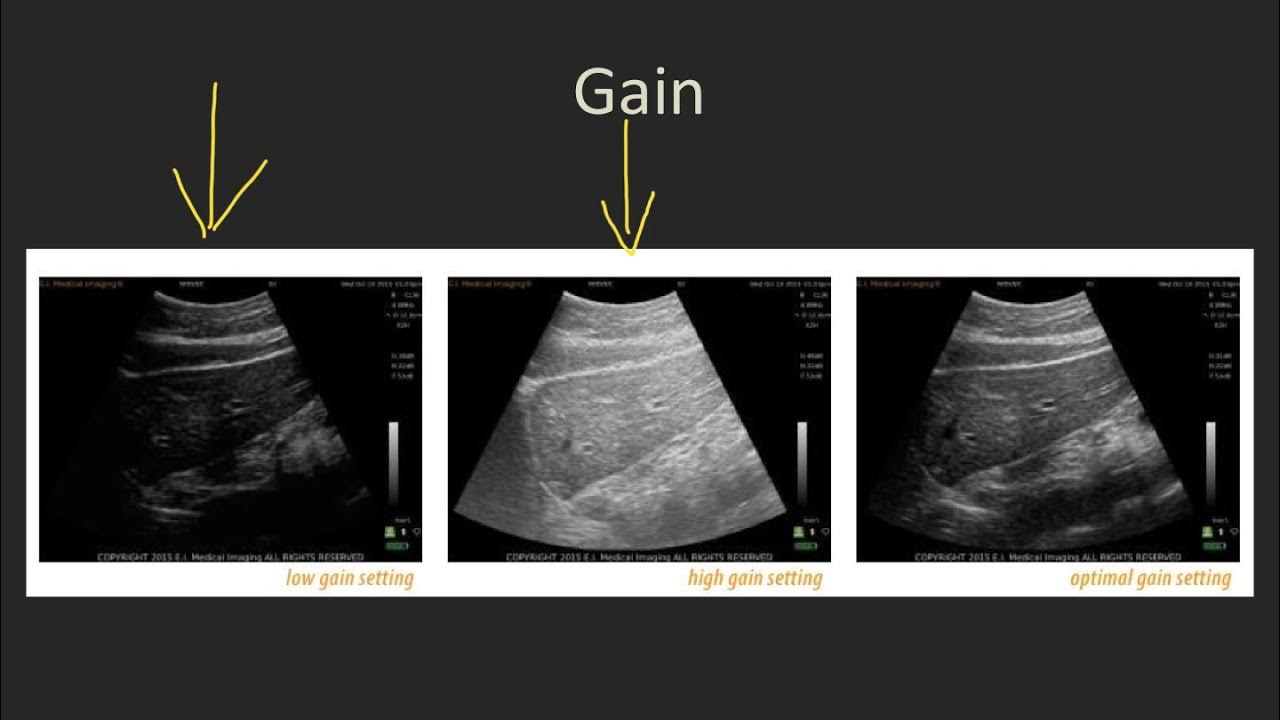

Ultrasound Gain And Depth . The top rows of the time gain compensation. So rather than brightening the monitor, the image on the screen is whitened. This web page explains the basic terms and concepts of ultrasound imaging and how to optimize the image quality using different knobs and buttons. Gain is a uniform amplification of the ultrasonic signal that is returning to the transducer after it travels through the tissue. Learn more about depth and focus in our blog article. Proper imaging requires the examiner to adjust the signal gain, which exists for each of the three us. Learn the basic principles of ultrasound physics and how they affect image quality and resolution. It covers topics such as gain, tgc, focal zone,.

This web page explains the basic terms and concepts of ultrasound imaging and how to optimize the image quality using different knobs and buttons. Learn more about depth and focus in our blog article. Proper imaging requires the examiner to adjust the signal gain, which exists for each of the three us. Learn the basic principles of ultrasound physics and how they affect image quality and resolution. Gain is a uniform amplification of the ultrasonic signal that is returning to the transducer after it travels through the tissue. So rather than brightening the monitor, the image on the screen is whitened. It covers topics such as gain, tgc, focal zone,. The top rows of the time gain compensation.